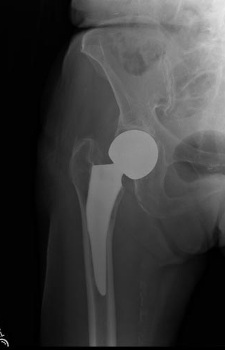

Example X-Ray Images

Partial Hip Replacement (Hemi-Arthroplasty)